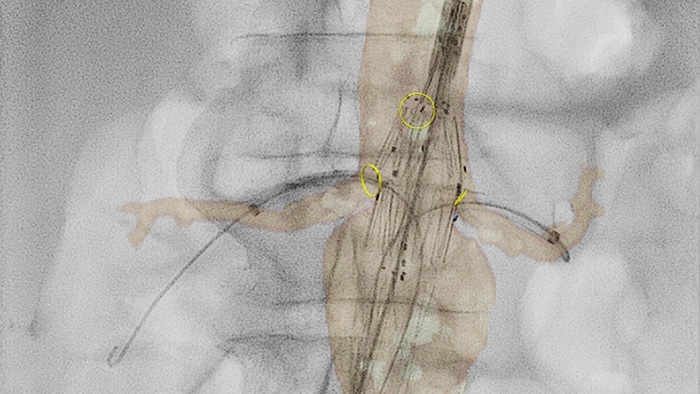

VesselNavigator allows reuse of 3D vascular anatomical information from existing CTA and MRA datasets as a 3D roadmap overlay on a live X-ray image. With its excellent visualization, VesselNavigator provides an intuitive and continuous 3D roadmap to guide you through vasculature.